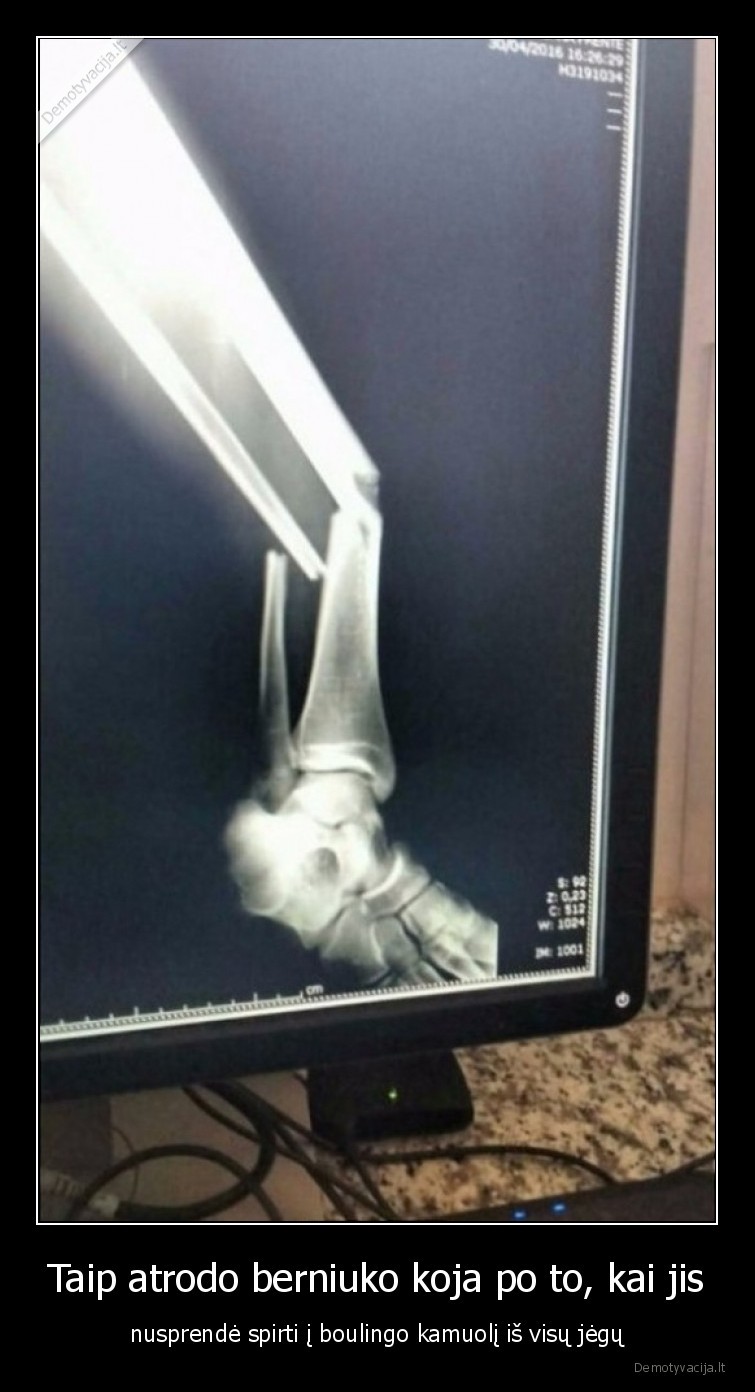

Taip atrodo berniuko koja po to, kai jis - nusprendė spirti į boulingo kamuolį iš visų jėgų